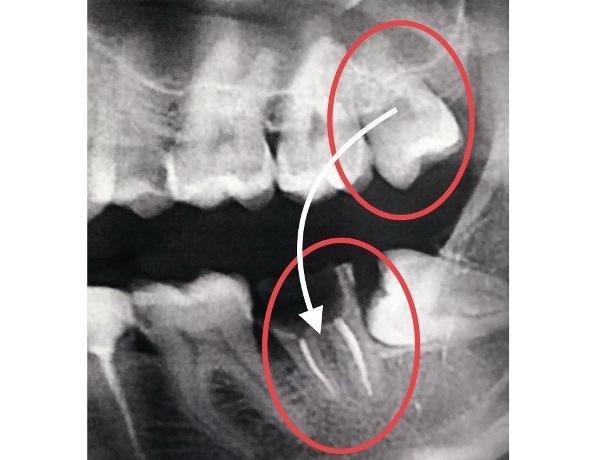

Реплантация зуба: Этапы и особенности операции